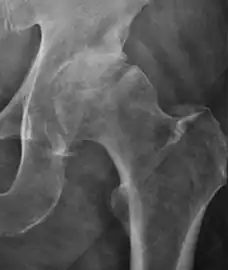

Plain radiography allows us to categorize the hip as normal or dysplastic or with impingement signs (pincer, cam, or a combination of both). Besides these, pathologic processes like osteoarthritis, inflammatory diseases, infection, or tumors can also be identified (Figure 1).[1]

Figure 1.

Radiography in normal hip

X-ray in pincer impingement type of hip dysplasia

X-ray of cam

Hip in osteoarthritis

Septic arthritis